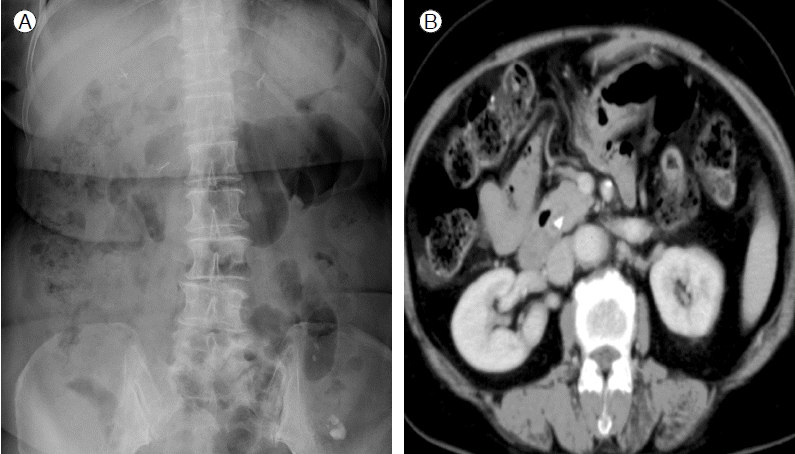

71세 여자가 개인의원에서 건강검진 목적으로 시행한 복부초음파검사에서 총담관 결석이 발견되어 입원하였다. 환자는 6년 전 급성 결석성 담낭염 진단하에 복강경담낭절제술을 시행 받았다. 입원 당시 활력징후는 정상이었고, 혈액검사에서는 AST 73 IU/L, ALT 63 IU/L, r-GT 483 IU/L, 알칼리 포스파타아제 780 IU/L이었으나, 특별한 증상을 호소하지는 않았다. 복부 X-선 검사에서 우상복부에 2개의 외과적 클립이 관찰되고 2번째 요추 우측에서 또 다른 한 개의 클립이 관찰되었고, 복부 컴퓨터단층촬영에서 경도의 총담관 확장과 총담관 내에 금속성 인공물이 관찰되었다(Fig. 1). 내시경 역행담도조영술에서 총담관의 확장이 관찰되고, 총담관 내 중심부에 외과적 클립으로 생각되는 방사선비투과 물질을 포함한 타원형의 음영결손이 관찰되었다. 내시경괄약근절개술을 시행한 후 바스켓과 회수용 풍선 카테터를 이용하여 결석을 제거하였다(Fig. 2). 제거된 결석은 갈색석이었다.

Figure 2.

ERCP finding. (A) There is a single large ellipsoidal filling defect with internal core of surgical metal clip in the proximal common bile duct. (B) The stone was retrieved by sweeping bile duct using retrieval balloon catheter after endoscopic sphincterotomy, and the extracted stone was a brown pigment stone.